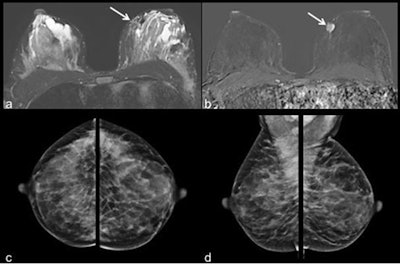

"By using additional postprocessing methods, i.e., supplemental subtraction images, the high background enhancement can be eliminated to facilitate diagnostics for better tumor visualization," they wrote (European Radiology, 18 September 2018). "Ultrasound remains a reliable and readily available diagnostic tool, while interpretations of mammography can be difficult in these patients due to high parenchymal density."

They investigated the detectability of breast cancer in lactating glandular tissue with a focus on enhancement kinetics of background parenchyma and tumor lesions by using pre- and postcontrast acquisitions and their derived postprocessed subtraction images. They evaluated the detectability of lesions in the postprocessed images and assessed the value of additionally calculated supplemental subtraction images. All of this was compared with ultrasound and mammography findings.

Kinetics measured plateau (n = 8), continuous (n = 10), and not quantifiable (n = 1). Tumor kinetics presented washout (n = 17) and plateau (n = 2). Eighteen of 19 tumors were identified on the supplemental subtraction images.

Regarding the use of supplemental subtraction, they identified malignant lesions in 18 out of 19 patients, leading to a detection rate of 95%. When comparing conventional versus supplemental subtraction images, the researchers found no difference in measured tumor size.

"No further lesion was detected in the additionally calculated supplemental subtraction images in our collective," they wrote. "Nevertheless, this method of reducing the background parenchymal enhancement to a minimum and displaying the area of washout kinetics can be of great help to securely detect a malignant lesion, rule out satellite lesions, or identify tumor spread in the surrounding tissue, especially when background parenchymal enhancement is marked (which is the case in lactating women)."